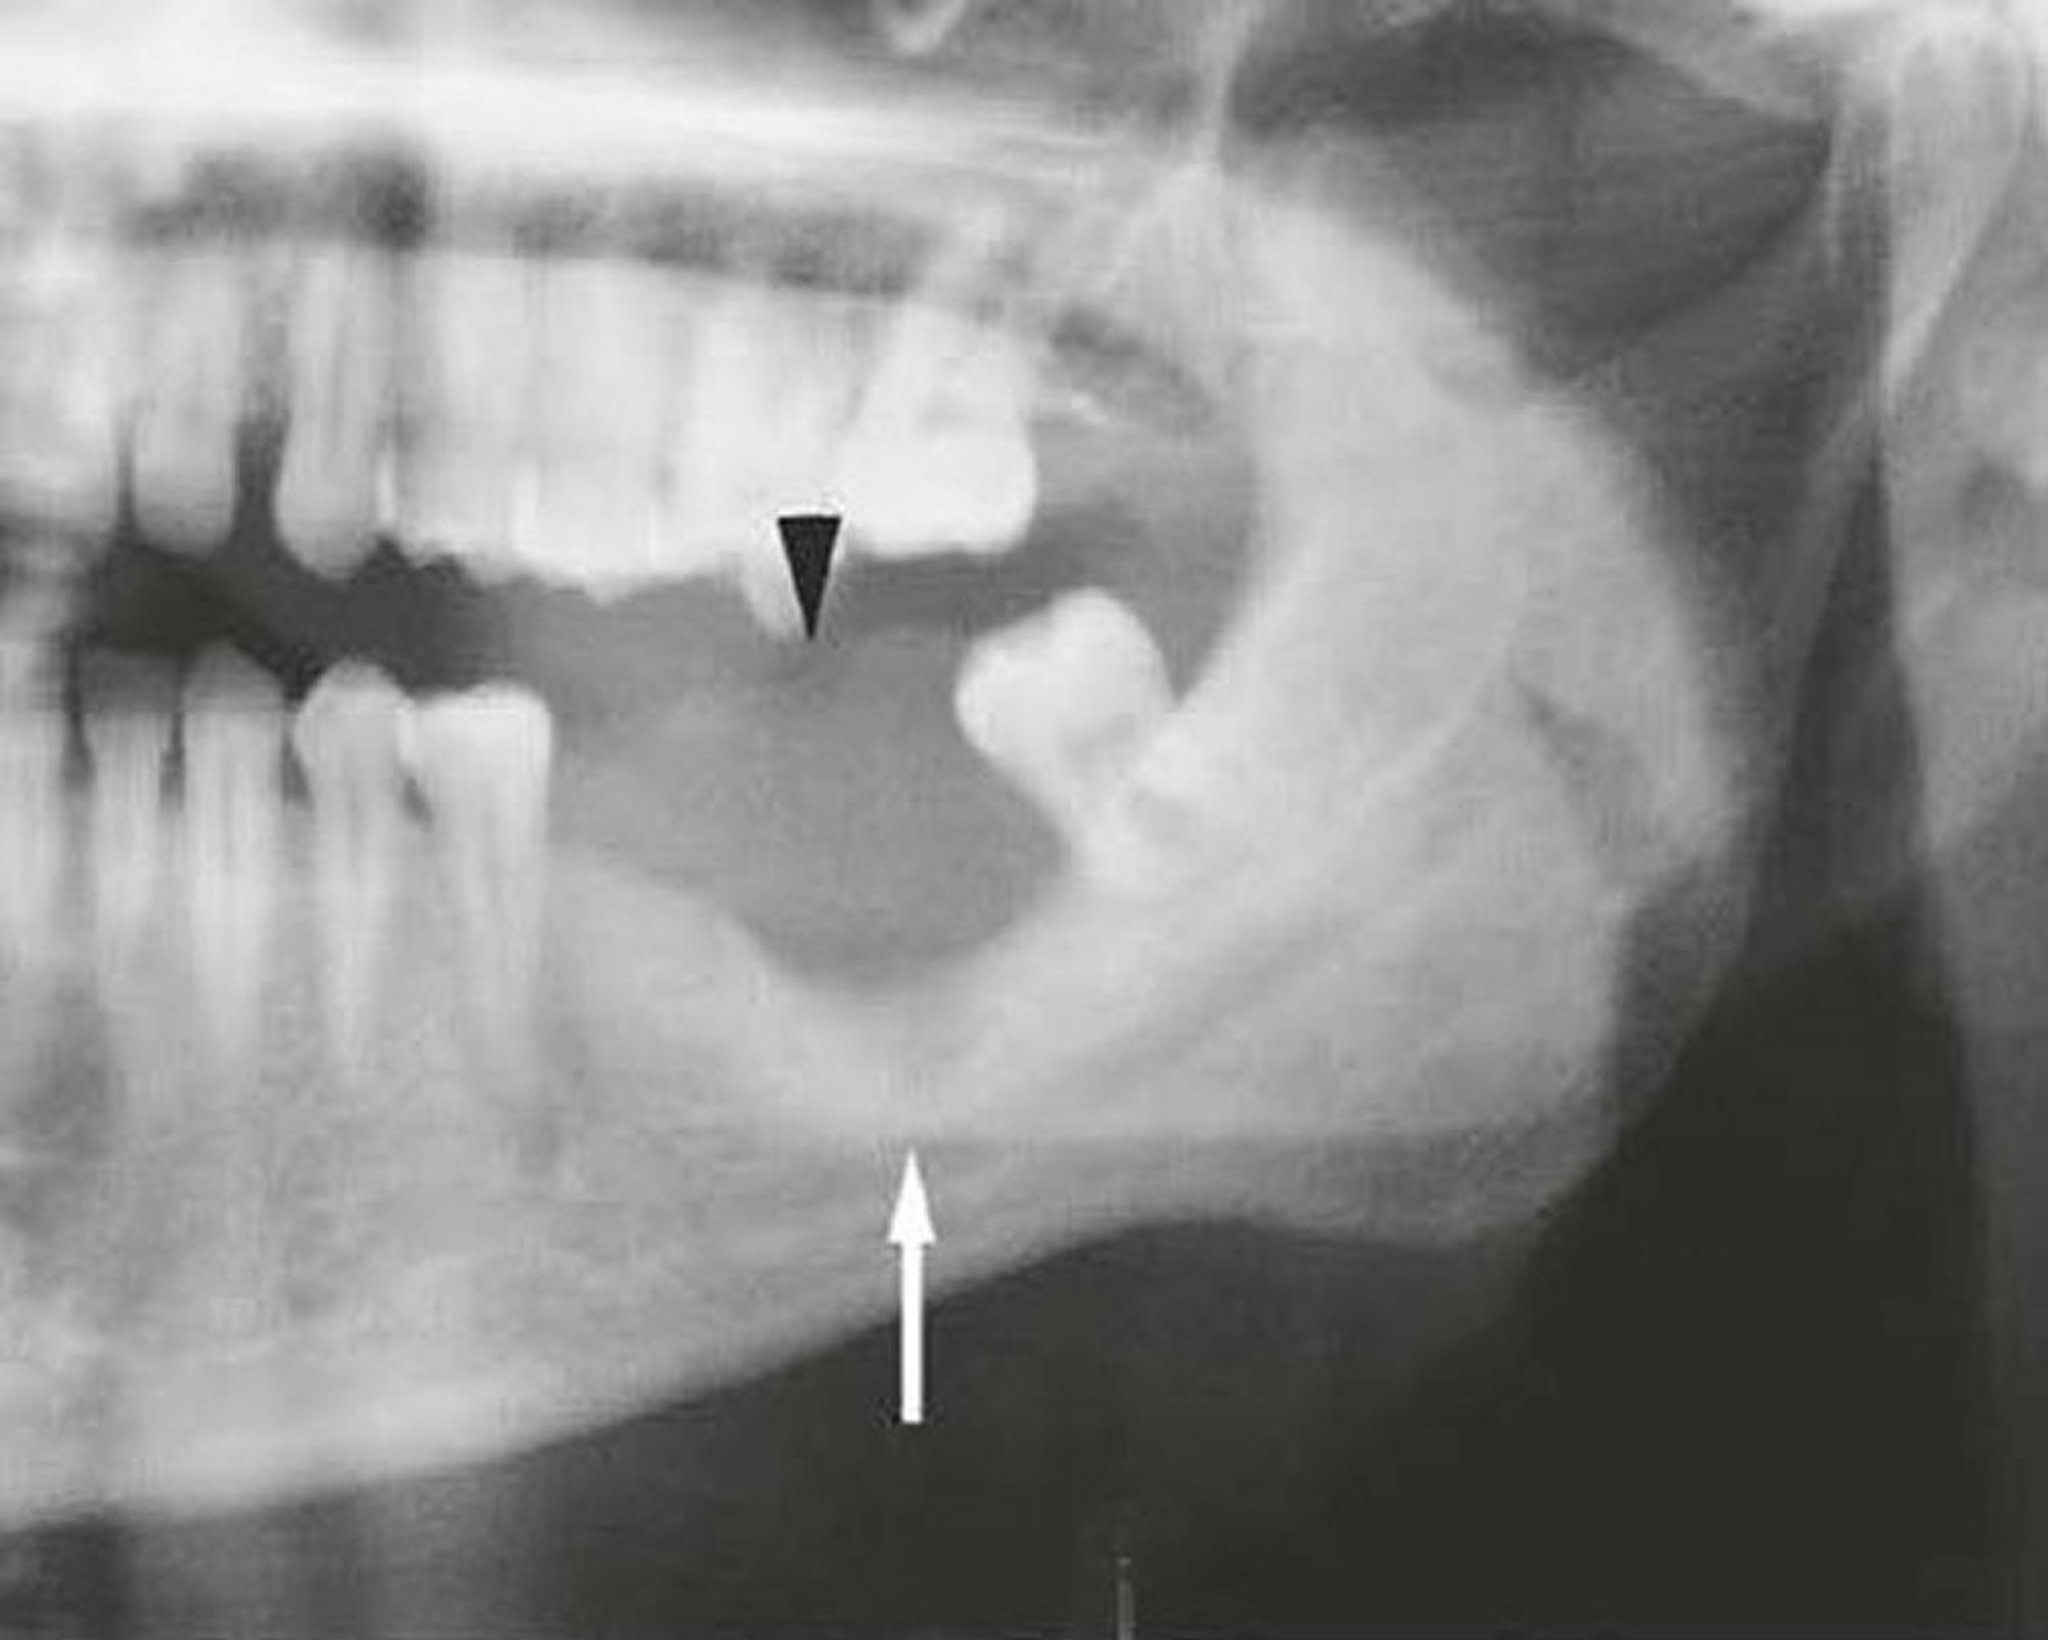

Essa imagem de uma mandíbula invadida por carcinoma de células escamosas mostra uma massa de tecidos moles (seta) e destruição óssea (flecha).